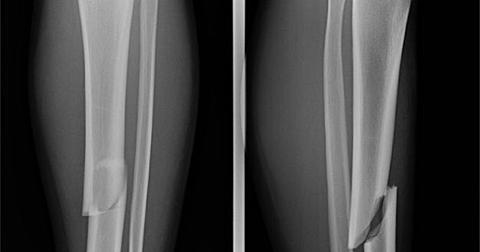

骨折する箇所

- 背骨(椎体=胸椎と腰椎)

- 手首の骨折

- 股のつけ根の骨折(大腿骨頚部骨折)